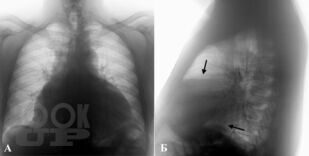

Обобщена современная информация о многочисленных вариантах заболеваний перикарда. Приводятся результаты собственных эпидемиологических наблюдений и данные зарубежных и отечественных специалистов. Рассмотрены методы диагностики и лечения заболеваний перикарда согласно последним рекомендациям Европейского кардиологического общества (2015), Бразильского кардиологического общества (2013), Американского эхокардиографического общества (2013) и Европейской ассоциации сердечно-сосудистой визуализации (2013). Книга иллюстрирована схемами, электрокардиограммами, эхограммами.